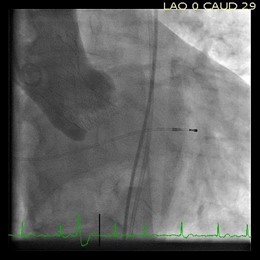

El Servicio de Cardiología del Hospital Universitario Central de Asturias (HUCA) ha implantado con éxito este mes, por primera vez en España, un nuevo modelo de válvula aórtica de mayor tamaño que las normales, diseñado especialmente para pacientes con anillos aórticos más grandes que la mayoría de la población. La nueva válvula es de 34 milímetros.

Según ha informado el Gobierno asturiano a través de una nota de prensa, hasta ahora, las intervenciones en este tipo de pacientes únicamente se podían realizar mediante cirugía abierta, pero ahora ya es posible llevarlas a cabo de forma íntegra con catéteres que se introducen a través de arterias de la ingle.

Este avance supone un paso más en el desarrollo de una técnica que el HUCA ya desarrolló en enero de 2007, cuando el equipo dirigido por el cardiólogo César Morís se convirtió en el primero de España en tratar a los pacientes de estenosis aórtica con un implante percutáneo conocido como TAVI.